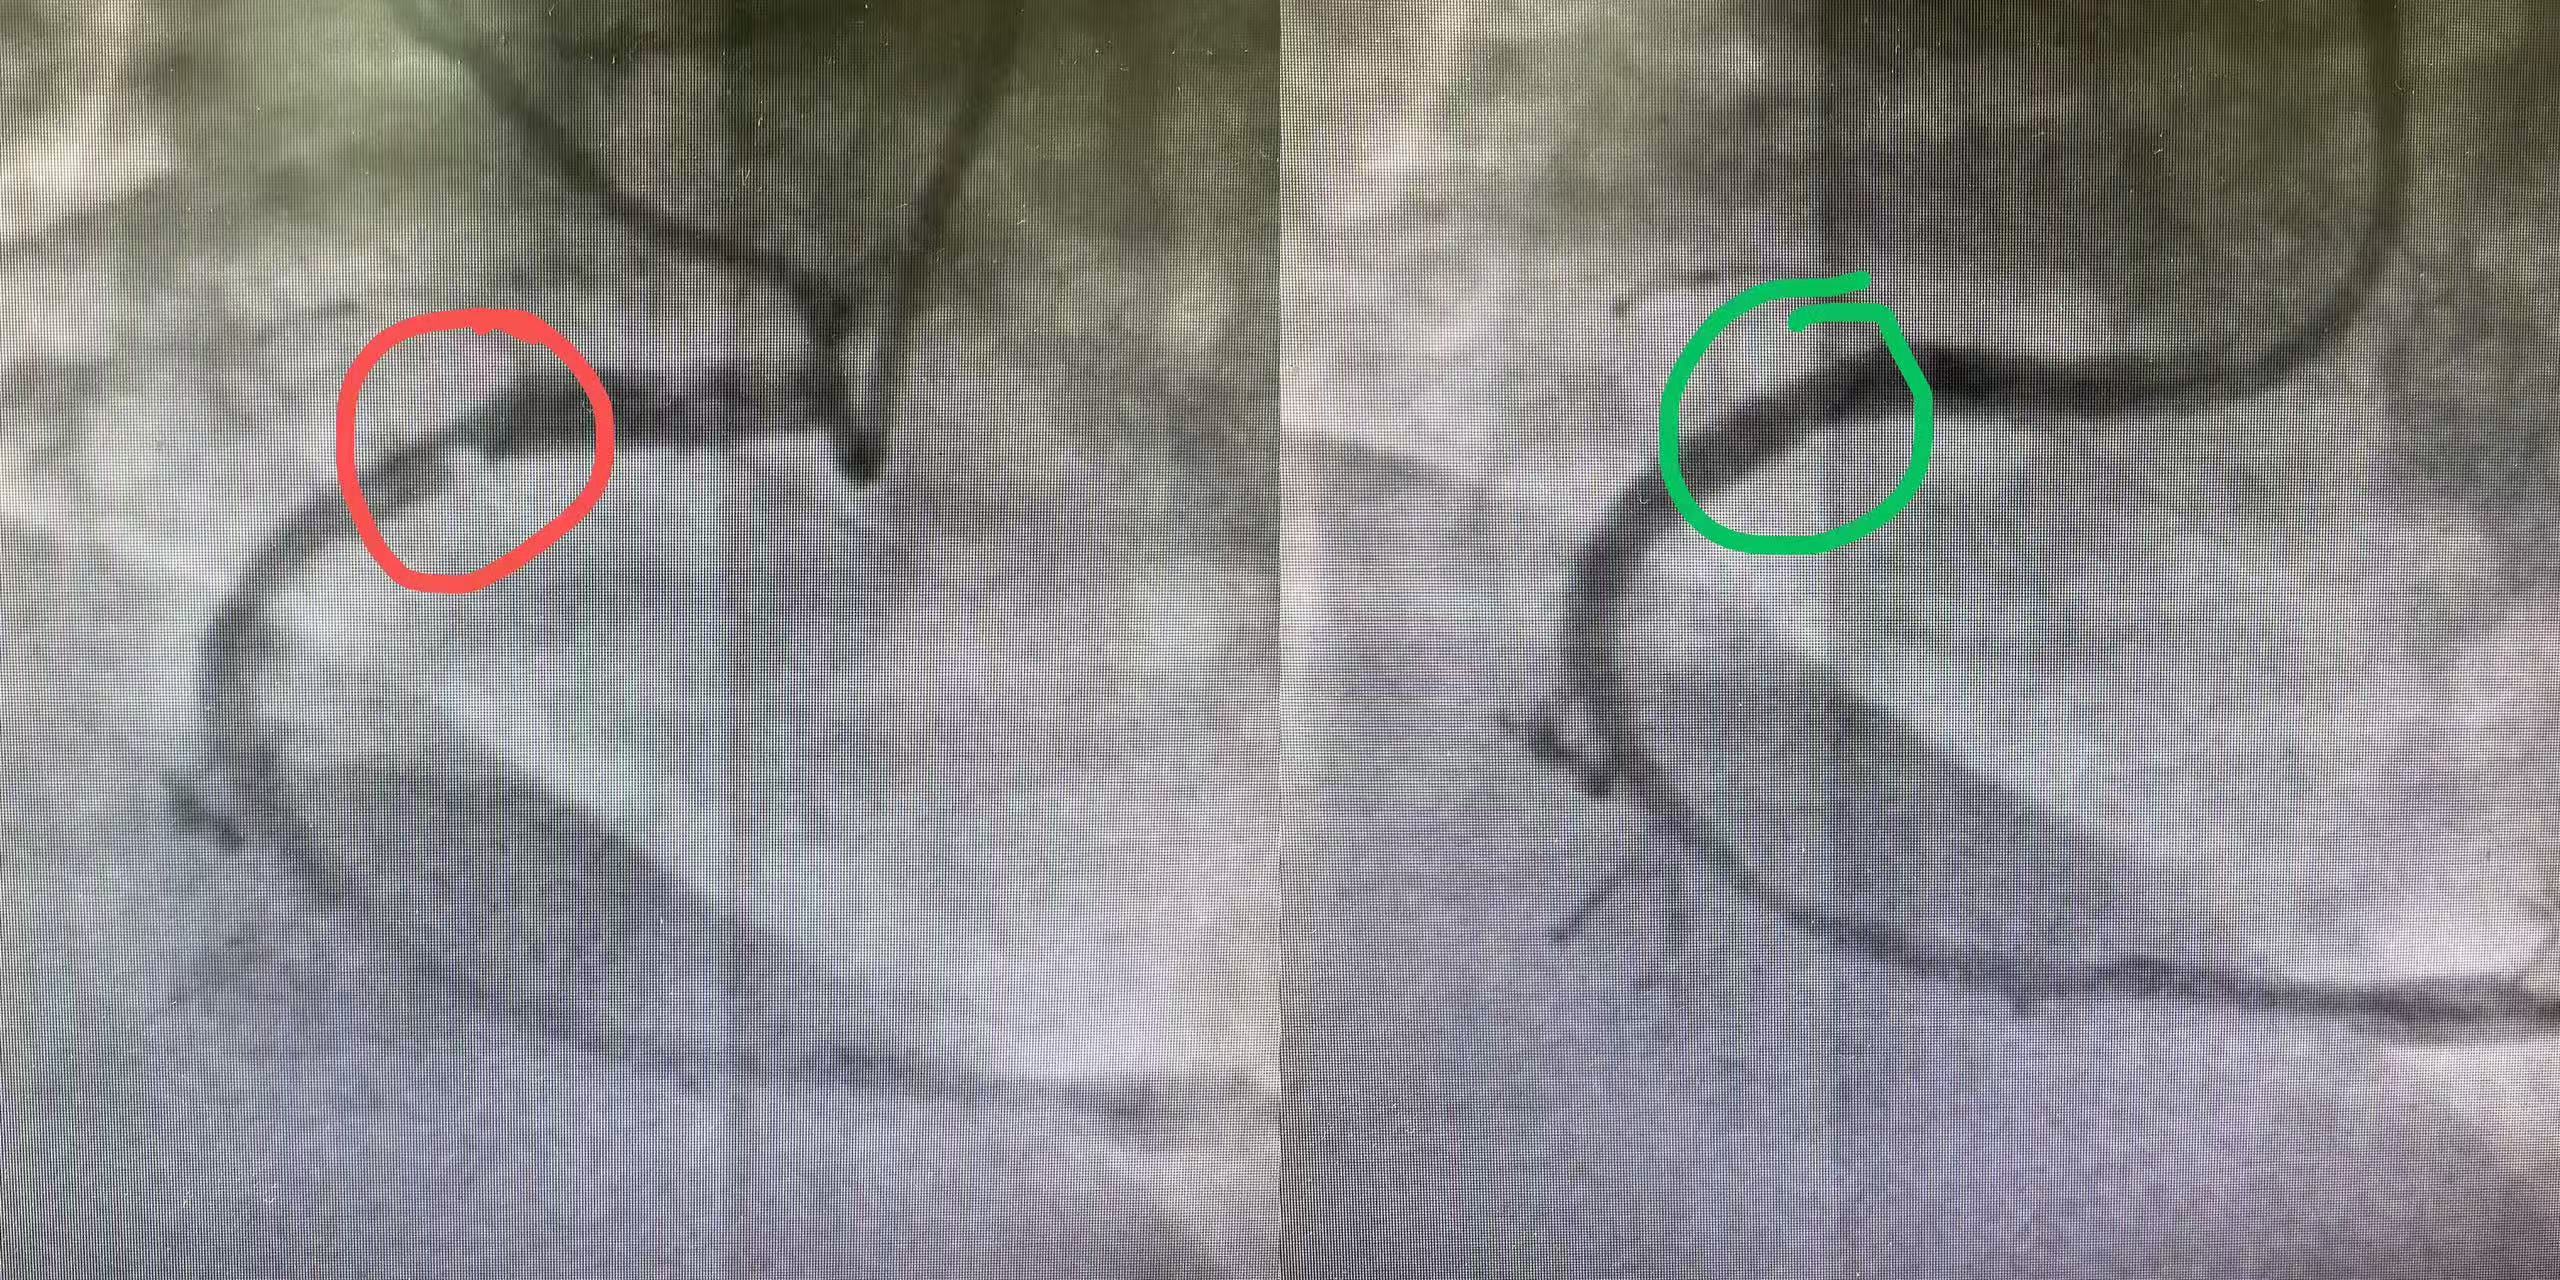

支架前(紅色)后(綠色)對比: